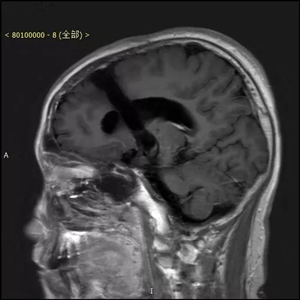

患者术前资料(下图)